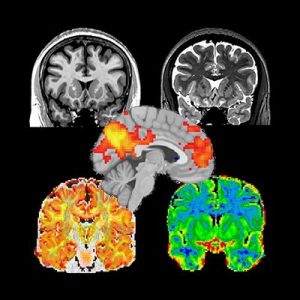

Morphometric Analysis

Population studies in neurodegenerative disease and neurodevelopment are supported by ongoing development of feature-specific and sensitive methods that help detect statistical deviations of the anatomical features from the “normal” brain.